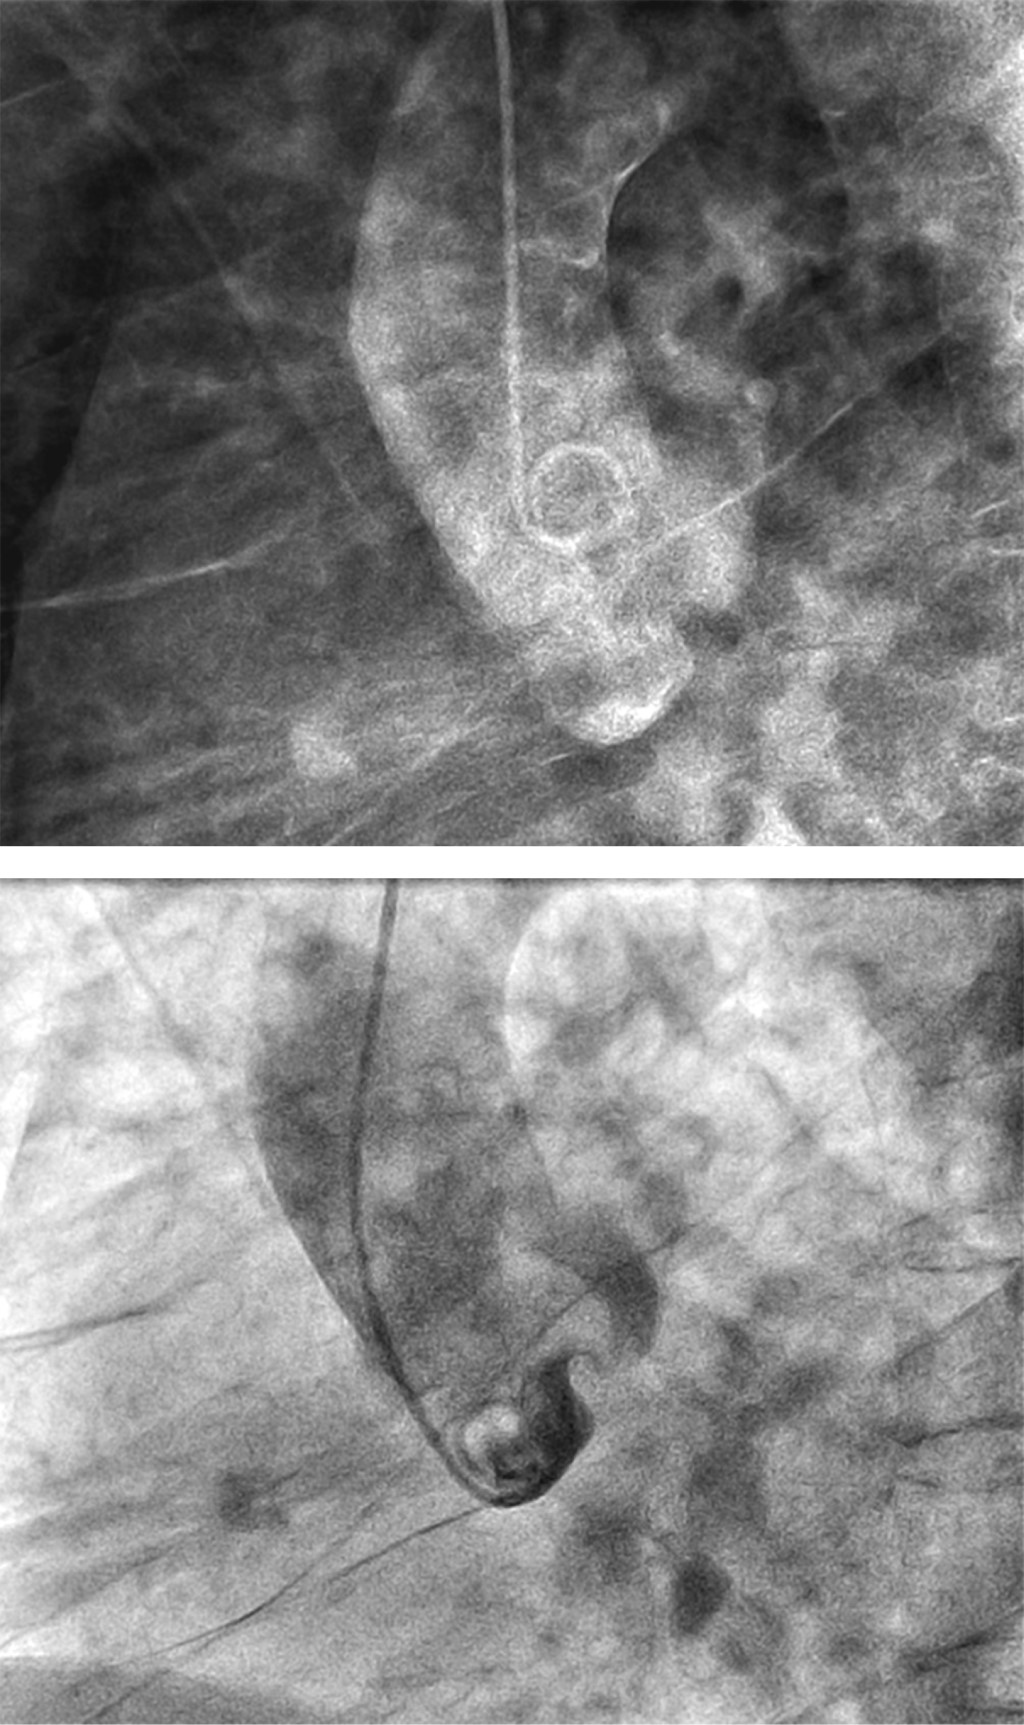

Ausencia congénita de la arteria coronaria derecha con oclusión total crónica de la arteria coronaria izquierda: un escenario clínico raro

En la literatura se han reportado pocos casos de ausencia de la arteria coronaria. Además, es infrecuente la ausencia de la arteria coronaria derecha (CD) con oclusión total crónica (OTC) de la arteria coronaria izquierda. Presentamos el caso de un paciente mexicano con antecedentes de dolor torácico inducido por el ejercicio, en quien se confirmó, mediante angiografía coronaria, una ausencia congénita de CD con OTC. El paciente fue dado de alta asintomático y permaneció así tras el tratamiento conservador. La ausencia de arterias coronarias resulta del desarrollo embrionario anormal, con diversas manifestaciones clínicas; la mayoría de los pacientes muestran síntomas de isquemia miocárdica. Este caso ilustra la importancia de la angiografía coronaria para el diagnóstico, que se considera el estándar de oro. Sin embargo, no existen pautas de tratamiento estandarizadas; se puede utilizar una terapia conservadora o de revascularización para tratar la afección. Debido a su incidencia extremadamente baja, es difícil determinar el pronóstico de esta anomalía coronaria.

Figura 1

Figura 2

Figura 3